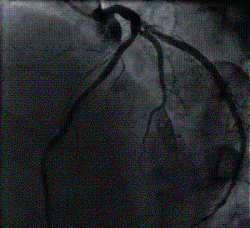

Coronary Angiography is a procedure to visualise the coronary arteries. The coronary arteries are the blood vessels that supply blood to the heart muscles. On ordinary chest X-ray films, the heart appears as a silhouette and the coronary arteries cannot be seen. To see the coronary arteries, a special dye or contrast medium is injected through a small tube (catheter) inserted into a large artery in the groin or the wrist. The catheter is then advanced to the heart and positioned at the mouths of the coronary arteries before injection is performed.

Coronary Angiography is therefore an invasive procedure. Sometimes, another procedure called a left ventriculography is performed at the same session, whereby a catheter is advanced into the left ventricle (the lower and larger heart chamber) and contrast medium is injected. This allows visualisation of the left ventricle and its contractions.

Coronary Angiography is carried out to determine whether there is any significant narrowing or blockage in the coronary arteries. Once determined, the doctor will decide on the best form of treatment.

It is also performed before Coronary Angioplasty (ballooning) is carried out to provide a 'road map' for guiding the Angioplasty procedure.